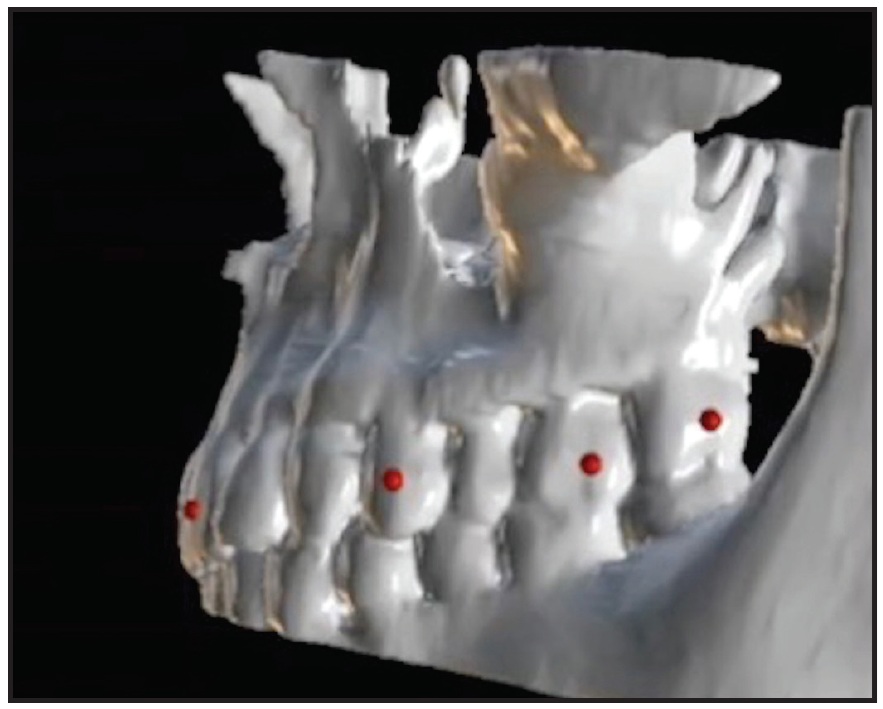

She displayed good facial symmetry and lateral buccal corridors on smiling, with a harmonic profile and adequate lip projection. The patient had a Class I molar relationship on both sides and moderate crowding in both arches. Cephalometric analysis confirmed good skeletal proportions in both the sagittal and vertical planes. The panoramic x-ray revealed an impacted upper right canine with mesial crown inclination. A CBCT surface rendering of the segmented maxillary teeth28 showed the canine to be in a palatal position, mesially inclined, with the crown just behind the roots of the lateral and central incisors and the root close to the apex of the first premolar. Analysis of the digital models with Maestro 3D† found excessive buccal crown torque of the upper molars and premolars on both sides, indicating dentoalveolar compensation for maxillary constriction (Fig. 7B).

Initial treatment goals included skeletal expansion of the maxillary arch and de-impaction of the upper right canine with maximum anchorage. Considering the patient’s age and dentoalveolar compensation, we decided to use a miniscrew-anchored device for optimal skeletal expansion. Two miniscrews would be inserted in the anterior paramedian region of the palate to support the expander.

Digital equivalents of two self-drilling miniscrews were selected with Blue Sky Plan’s “customize implant” feature. Using the coronal, sagittal, and axial views of the CBCT scans, the miniscrew orientation and insertion site were adjusted to obtain an area with adequate bone and to maintain a safe distance from the impacted canine. Adjustments were also made in the 3D view to verify proper inclination of the miniscrews in relation to the main axes of the first molars,29 as well as full coverage of the transmucosal miniscrew neck and free space between the miniscrew heads and the lateral slope of the palatal mucosa. Next, the surgical guide was digitally designed and 3D-printed*** as described above.